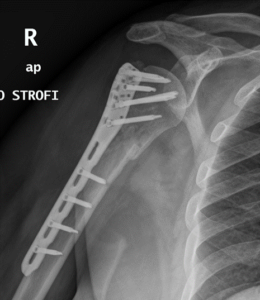

ΚΑΤΑΓΜΑ ΒΡΑΧΙΟΝΙΟΥ ΚΕΦΑΛΗΣ (ΠΛΑΚΑ-ΒΙΔΕΣ ΤΥΠΟΥ PHILOS)

Πρόκειται για γυναίκα ασθενή 45 ετών που μετά από πτώση εξ ιδίου ύψος, υπέστη υποκεφαλικό κάταγμα βραχιονίου κεφαλής με μεγάλη παρεκτόπιση.

Η ασθενής αντιμετωπίστηκε χειρουργικά με ανοικτή ανάταξη και εσωτερική οστεοσύνθεση με πλάκα τύπου philos.

Η ακτινογραφία επανεξέτασης στους 3 μήνες δείχνει πώρωση του κατάγματος σε πολύ καλή θέση, ενώ λειτουργικά η ασθενής δεν έχει πόνο και έχει ανακτήσει πλήρες εύρος κίνησης.